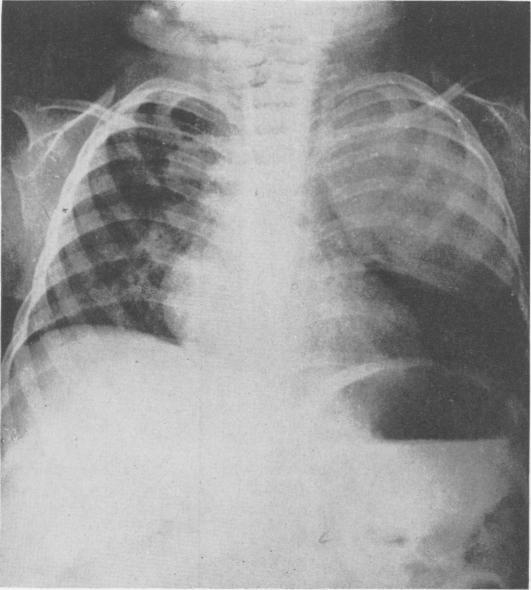

Bronchiogenic Cysts of the Mediastinum.

Ann Surg. 1948 Mar;127(3):476-502. doi: 10.1097/00000658-194803000-00010.